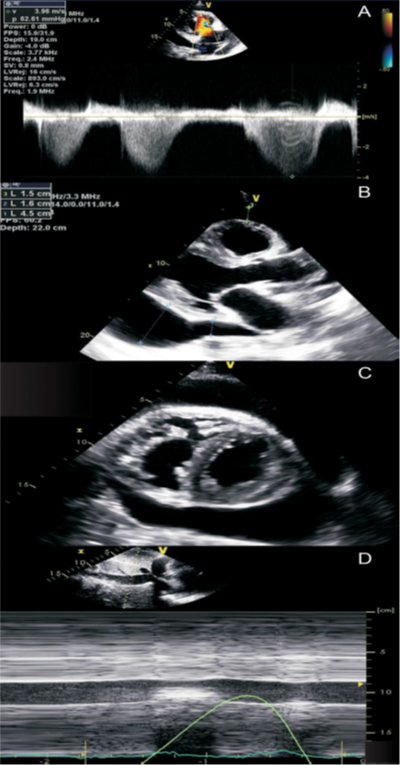

1. Перикардиальный выпот

Большое количество выпота в полости перикарда (эхонегативное пространство в диастолу более 20 мм), тампонада сердца, наряду с повышением температуры более 38°С, подострым течением, отсутствием эффекта от нестероидных противовоспалительных препаратов в течение 7 дней являются факторами неблагоприятного прогноза [136, 137, 93]. А при наличии хотя бы одного фактора неблагоприятного прогноза требуются госпитализация и поиск причины [1] (Приложение А3-14).

Наличие выпота в перикарде при тампонаде сердца может быть легко идентифицировано при ЭхоКГ-исследовании. Как правило, сердце имеет нормальные размеры. При этом определяются небольшие размеры предсердий и желудочков из-за недостаточного их заполнения кровью в диастолу, но отмечается их хорошая систолическая функция (компенсаторный гиперкинез стенок).

Если выпот не очень большой, развитие тампонады определяет скорость накопления жидкости, а не ее количество. Если жидкость накапливается быстро, возможно развитие тампонады сердца с небольшим выпотом в перикард с расхождением его листков всего лишь на 10 мм. И наоборот, тампонада сердца может не развиться даже при большом перикардиальном выпоте, если он накапливается медленно. Как правило, количество выпота в перикарде легко оценить в диастолу при измерении величины выпота между его листками в сантиметрах (перпендикулярно стенкам желудочков), обычно в парастернальной позиции:

1) минимальный перикардиальный выпот обычно видно только в систолу и без гемодинамических последствий;

2) расхождение листков перикарда <1 см соответствует примерно 300 мл выпота;

3) расхождение листков перикарда на 1–2 см — около 500 мл выпота;

4) расхождение листков перикарда на 2 см — обычно соответствует более 700 мл выпота.

5) Симптом «качающегося сердца» возникает при большом перикардиальном выпоте, когда создаются условия для чрезмерных колебательных движений сердца. Это состояние часто сопровождается тампонадой и электрической альтернацией на ЭКГ.

При нарастании выпота перикарда ЭхоКГ визуализация подтверждает формирование тампонады, что проявляется:

1) стабильным расширением нижней полой вены, которая значимо не спадается на высоте вдоха;

2) уменьшенным объемом прямого трансмитрального кровотока в ЛЖ, выявляемым при допплеровском исследовании;

3) компрессией во время диастолы ПЖ, или его коллабированием в тяжелых случаях;

4) коллабированием правого предсердия (ПП) в систолу [142].

У пациентов с тампонадой сердца при дыхании могут выявляться значительные изменения размеров камер сердца. Так, при вдохе отмечается увеличение ПЖ с сопутствующим уменьшением размеров ЛЖ. Наоборот, во время выдоха ПЖ уменьшается в размерах с одновременным увеличением размеров ЛЖ.

Однако следует отметить, что в определенных условиях некоторые эхокардиографические особенности формирования тампонады сердца, такие как правожелудочковая компрессия, тяжелая легочная гипертензия и гипертрофия ПЖ могут отсутствовать (Приложение А3, рис. А3-8) [142].

Обычно при тампонаде сердца в разные фазы дыхания наблюдаются значительные изменения трансмитрального и транстрикуспидального потоков. Во время первого сокращения сердца после вдоха максимальная скорость трансмитрального пика E уменьшается более чем на 30%, в то время как во время первого сердечного сокращения после выдоха максимальная скорость транстрикуспидального пика E уменьшается более, чем на 60% [142, 143].